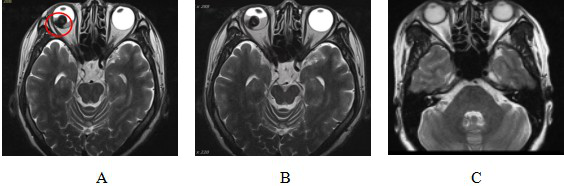

Figure 6 Comparison of MRI before and after CIRT treatment for malignant melanoma of choroid

Note: Figure 6A: MRI examination results before CIRT treatment showed: Abnormal signal nodules on the right side of the base of the eyeball. The red circle shows the extent of tumor invasion.

Figure 6B: MRI results after CIRT treatment showed: Abnormal signal nodules on the right lateral temporal side of the base of the eyeball, with little change compared with before.

Figure 6C: MRI examination 90 days after CIRT treatment showed that: the lesion disappeared and the efficacy was evaluated as CR.